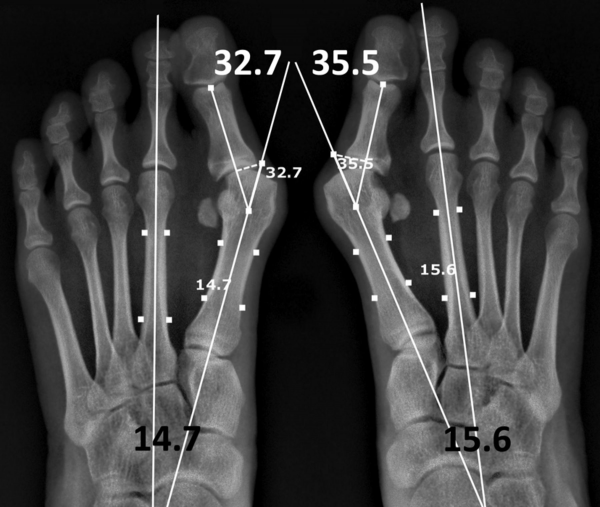

Рентгенологические обследование

Так называемая «косточка» - это халлюкс вальгус (hallux valgus), отклонение большого пальца стопы кнаружи (hallux valgus). Степень определяется через рентгенологическое исследование и расчётом угла отклонения. Косточка бывает не только у большого пальца, но и у мизинца. Причина такая же - плоскостопие, просто дискомфорта приносит меньше влдаельцу.